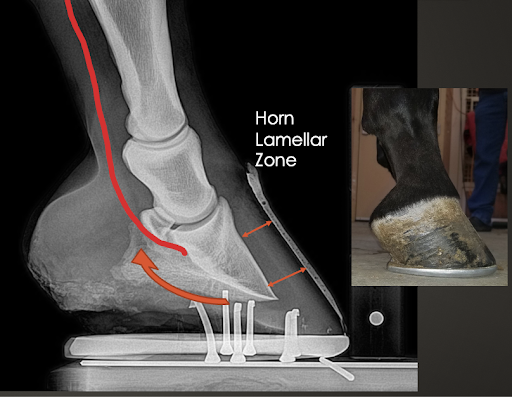

Horses with an upright foot have a horn lamellar zone that is wider at the bottom,

as well as some remodeling of the tip of the coffin bone. this comes from the action

of the deep digital flexor tendon. It pulls up, compresses the apex of the bone and

pulls the horn lamellar zone apart.

Club Foot/Mule Foot

Pittman often sees a mule-footed or club-footed type of horse in his clinic. This type of foot presents the opposite problem when compared with the foot with a long toe lever. These horses with an upright foot have a horn lamellar zone that is wider at the bottom. Also, there is some remodeling of the tip of the coffin bone. This comes from the action of the deep digital flexor tendon. It pulls up, compresses the apex of the bone and pulls the horn lamellar zone apart. The common pathology that Pittman sees is that a lot of times, horses will get thin soles or pedal osteitis at the tip of the coffin bone in this situation. They will have joint compression and some coffin joint disease. The load is so tight that it pulls the coffin bone in a palmar direction and pushes the navicular bone up into the bottom part of P2, and pushes it forward. Although coffin joint injections can alleviate pain for a certain period of time, mechanical intervention can be more helpful over the long term. On some horses, cartilage erosion in that part of the joint from the interaction can be found either in dissection or MRIs. These types of cases are where actual navicular bone disease cases are found, that have an actual bone cyst as opposed to biomechanically induced navicular.